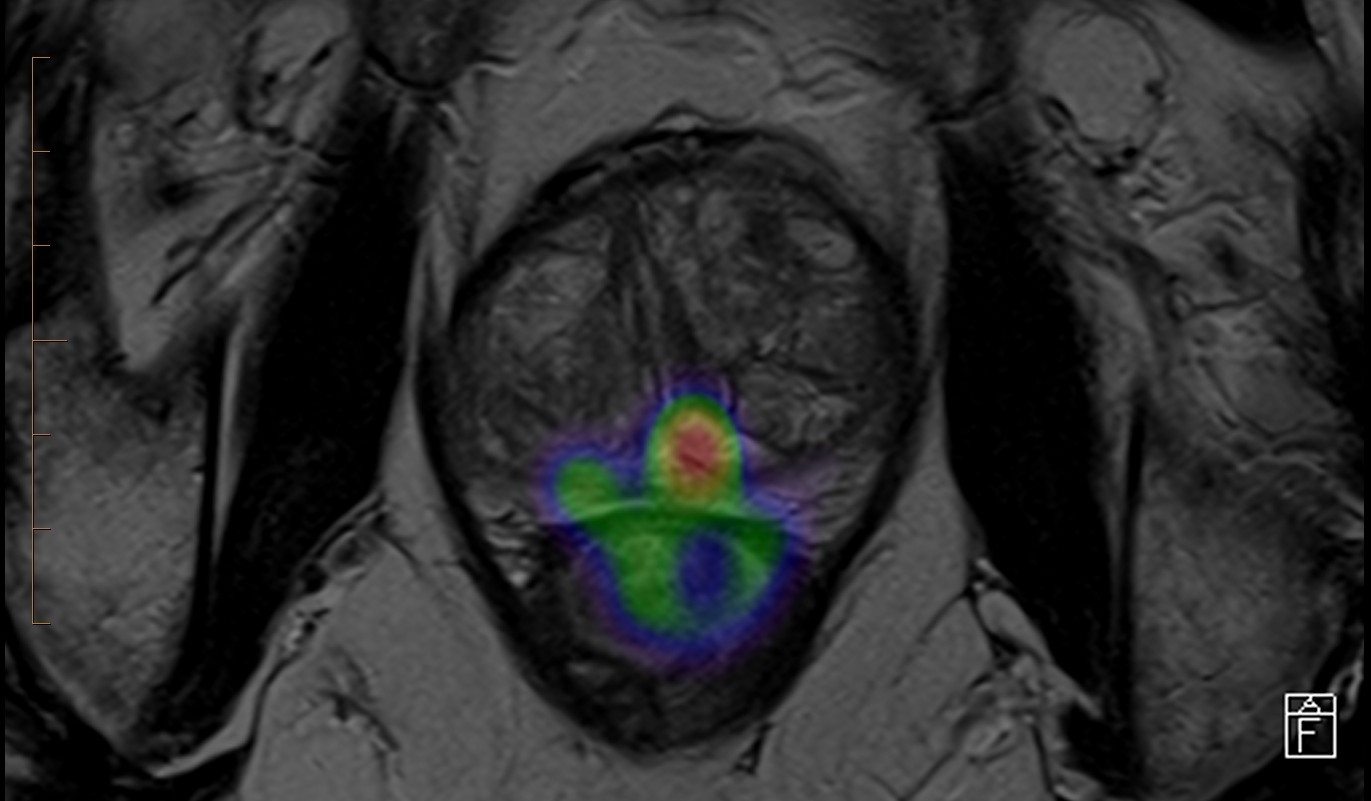

One of Australia’s most experienced cancer radiologists, Dr Lisa Tarlinton, has recently joined the team at Noosa Radiology. She has a special interest in prostate imaging, particularly the fusion of PSMA PET CT and prostate MRI.

“Using integrated AI software, I can combine the PET and MRI images to provide the greatest accuracy in the detection and staging of prostate cancer for our local patients.”

“Both the Siemens Lumina 3T MRI and the Biograph 450 Digital PET/CT are at the forefront on imaging technology,” Dr Tarlinton said.

“The digital PET / CT platform can pick up lymph node metastases as small as 1mm. We have also commenced theranostic treatment services for those prostate cancer patients who will benefit.